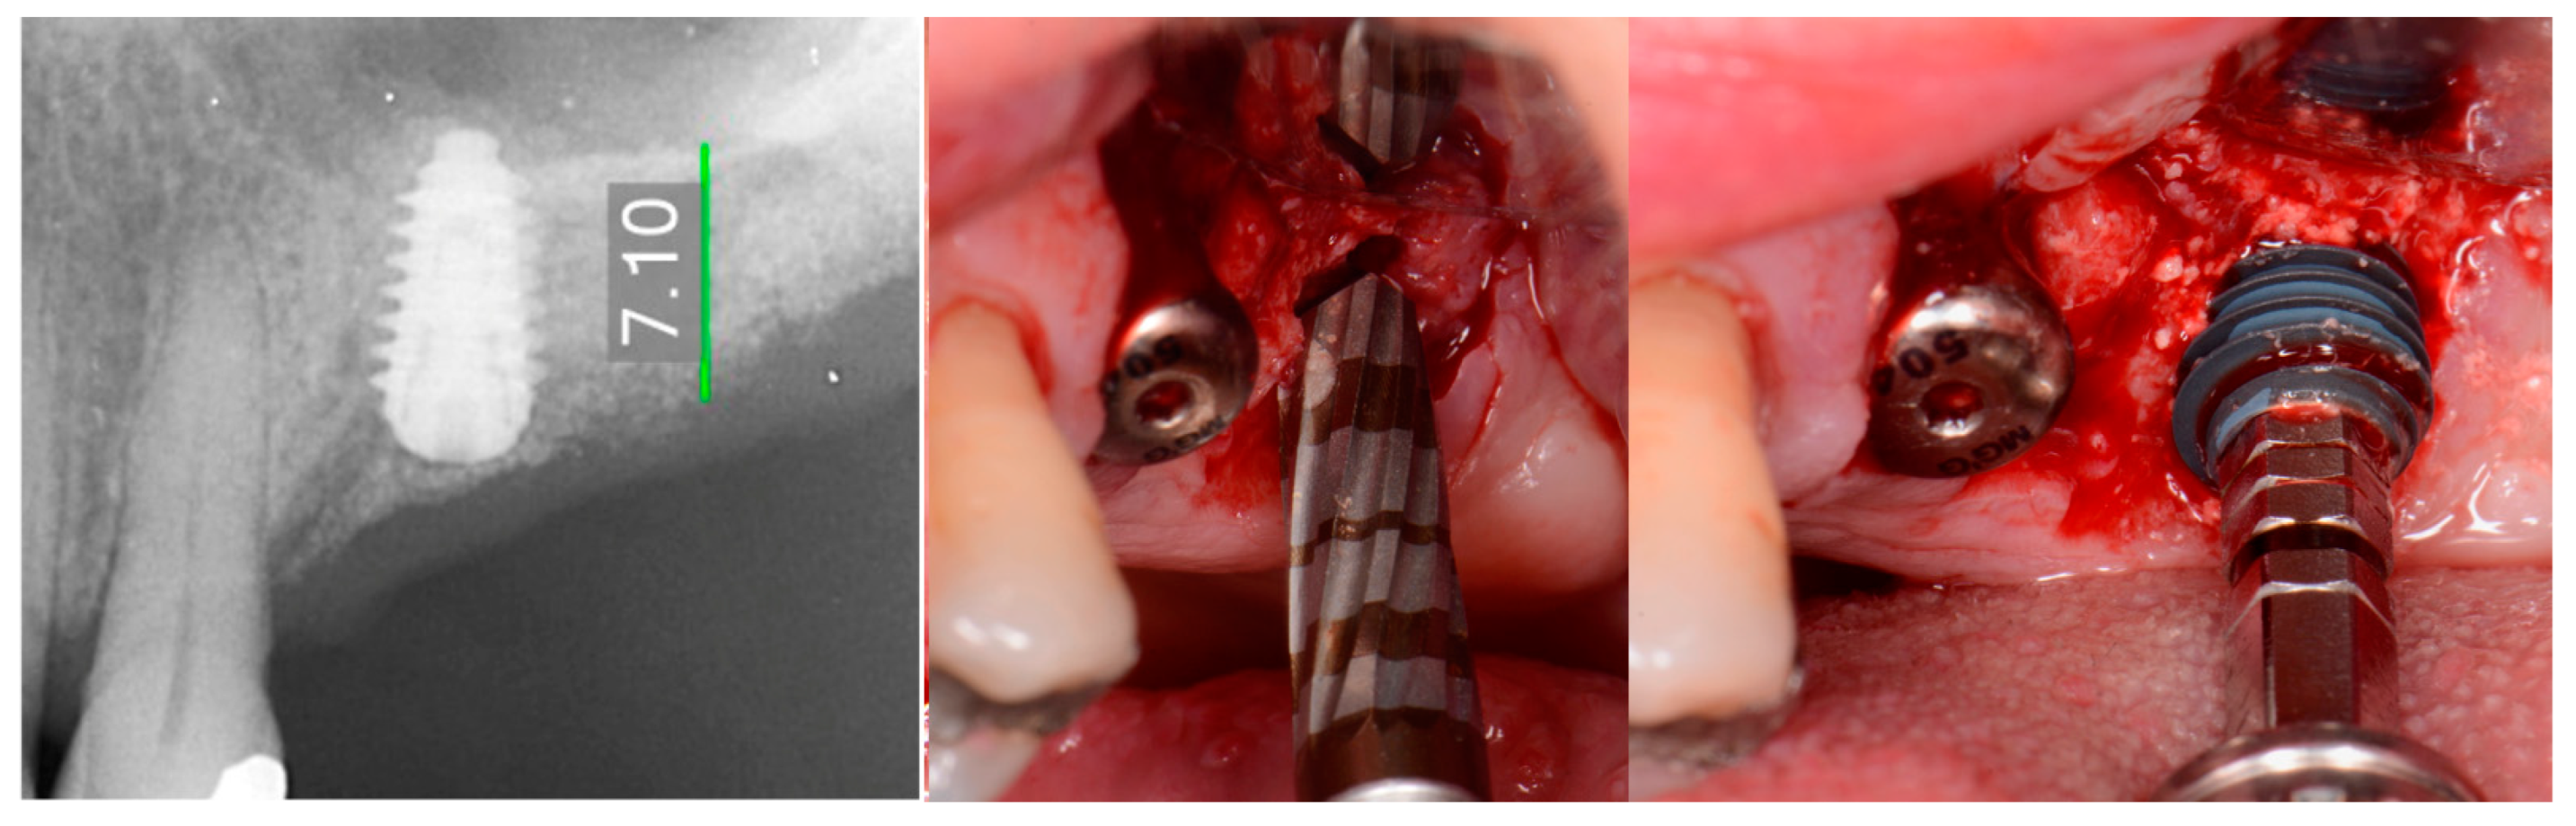

The patient returned at 10-weeks implant and graft placement and the soft tissue over the posterior quadrant was noted to be healed with no inflammation present (Figure 10 left). Following local anesthetic administration a full thickness flap was elevated and the previously grafted 2nd molar crestal area was filled with immature host bone (Figure 10 right). A radiograph was obtained, which noted a crestal height of 7.1 mm present (Figure 11 left). The 2nd molar site was prepared in a similar fashion as previously detailed, utilizing Densah burs to osseodensify the area and accomplish a crestal sinus augmentation and a 5 × 8.5 mm Anyridge implant was placed (Figure 11 middle and right). An impression of the 1st molar implant was obtained to initiate its restoration while the 2nd molar implant was integrating. A healing abutment was placed on the implant at the 1st molar and a cover screw on the 2nd molar implant and a radiograph obtained to document the clinical result to date (Figure 12).

Figure 11.

Radiograph demonstrating sufficient height of the ridge to allow primary stability of an implant placed at the 2nd molar with a crestal sinus augmentation at 10 weeks of graft healing (left), site preparation for the crestal sinus augmentation (middle) and implant placement into the site (right). Green line is the measurement of the height of the bone at that point between the crest and the sinus floor.